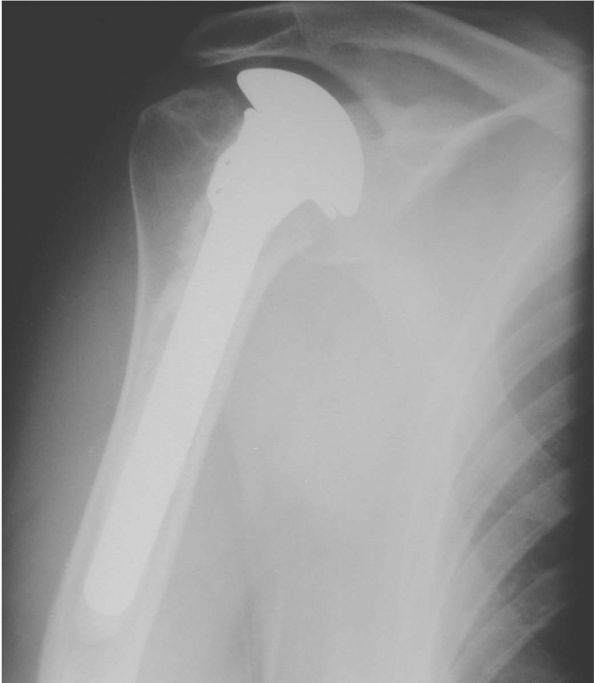

modular stem and head sizes (Figure 12-9).

predictable pain relief as well as functional improvement with an

intact functional rotator cuff and appropriate physical therapy. Both

total shoulder replacement and hemiarthroplasty can reliably provide

improvement in pain in more than 90% of patients; however, humeral head

replacement alone may result in less pain relief, relief that

deteriorates with time, and inferior functional outcomes (Figure 12-10).